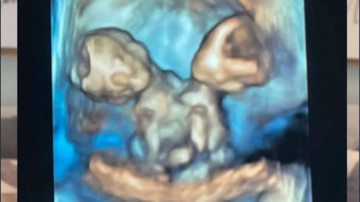

ABD'nin Michigan eyaletinde yaşayan Nicole ve Austin LeBlanc çifti, ilk kez bebek sahibi olacaklarını öğrendiklerinde büyük bir mutluluk yaşadı. Ancak bu sevinç kısa sürdü. Gebeliğin yedinci haftasında yapılan kontrolde, ultrasonda yalnızca bir kalp atışı duyulmasına rağmen ikiz gebelik şüphesi ortaya çıktı.

Kısa süre sonra Nicole, şiddetli karın ağrısıyla hastaneye kaldırıldığında gerçek ortaya çıktı. Anne adayı, aynı kalbi, karaciğeri, bağırsakları, diyaframı ve göbek kordonunu paylaşan ikiz kız bebeklere hamileydi.

Nicole, 32. haftada sezaryenle ikizlerini dünyaya getirdi. Maria Therese ve Rachel Clare isimleri verilen bebekler, doğum anında farklı tepkiler verdi.